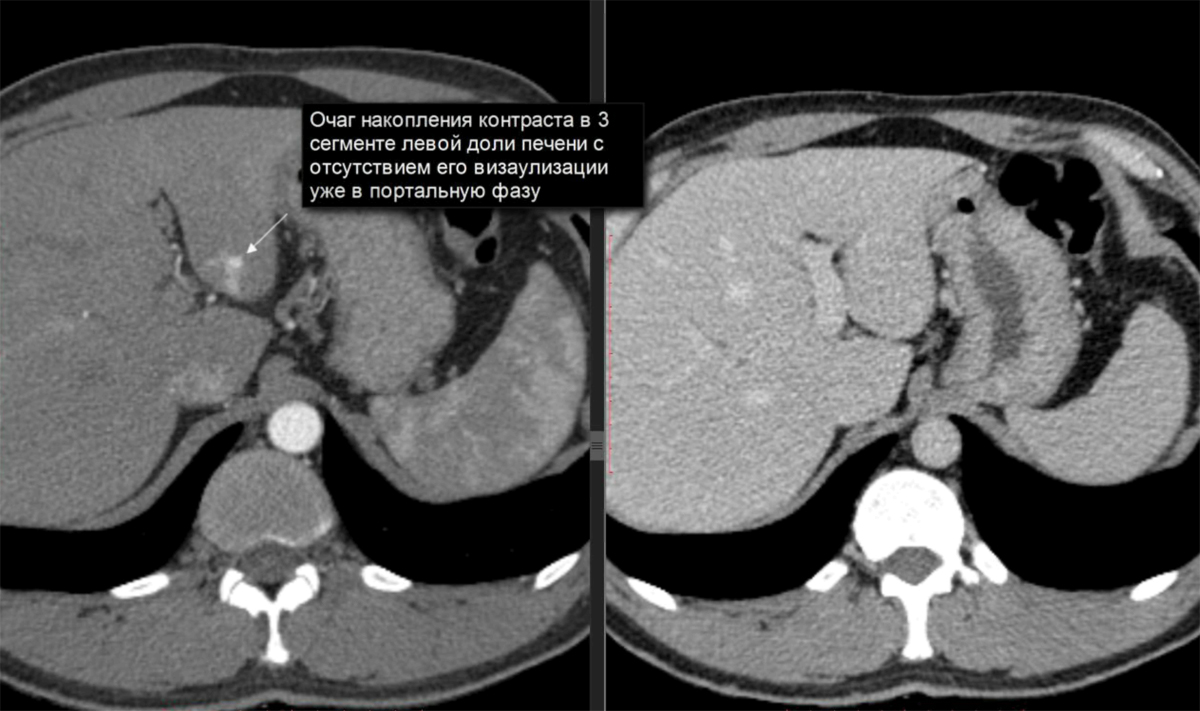

Методы динамического контрастирования печени на МРТ

Раздел: Снимки-подсказки